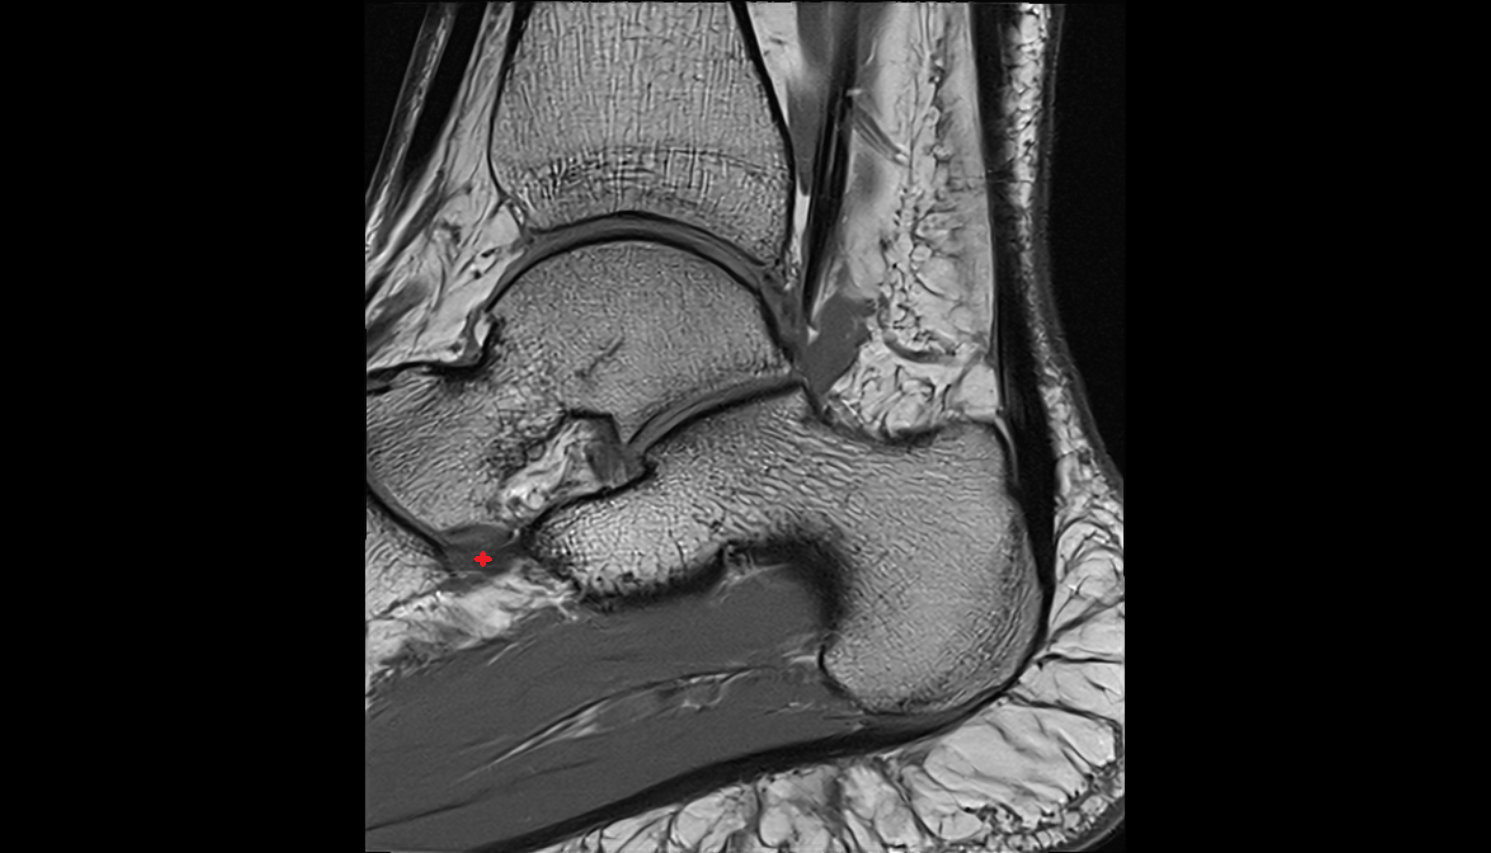

- Ankle joint

- Talus

- Calcaneus

- Achilles tendon